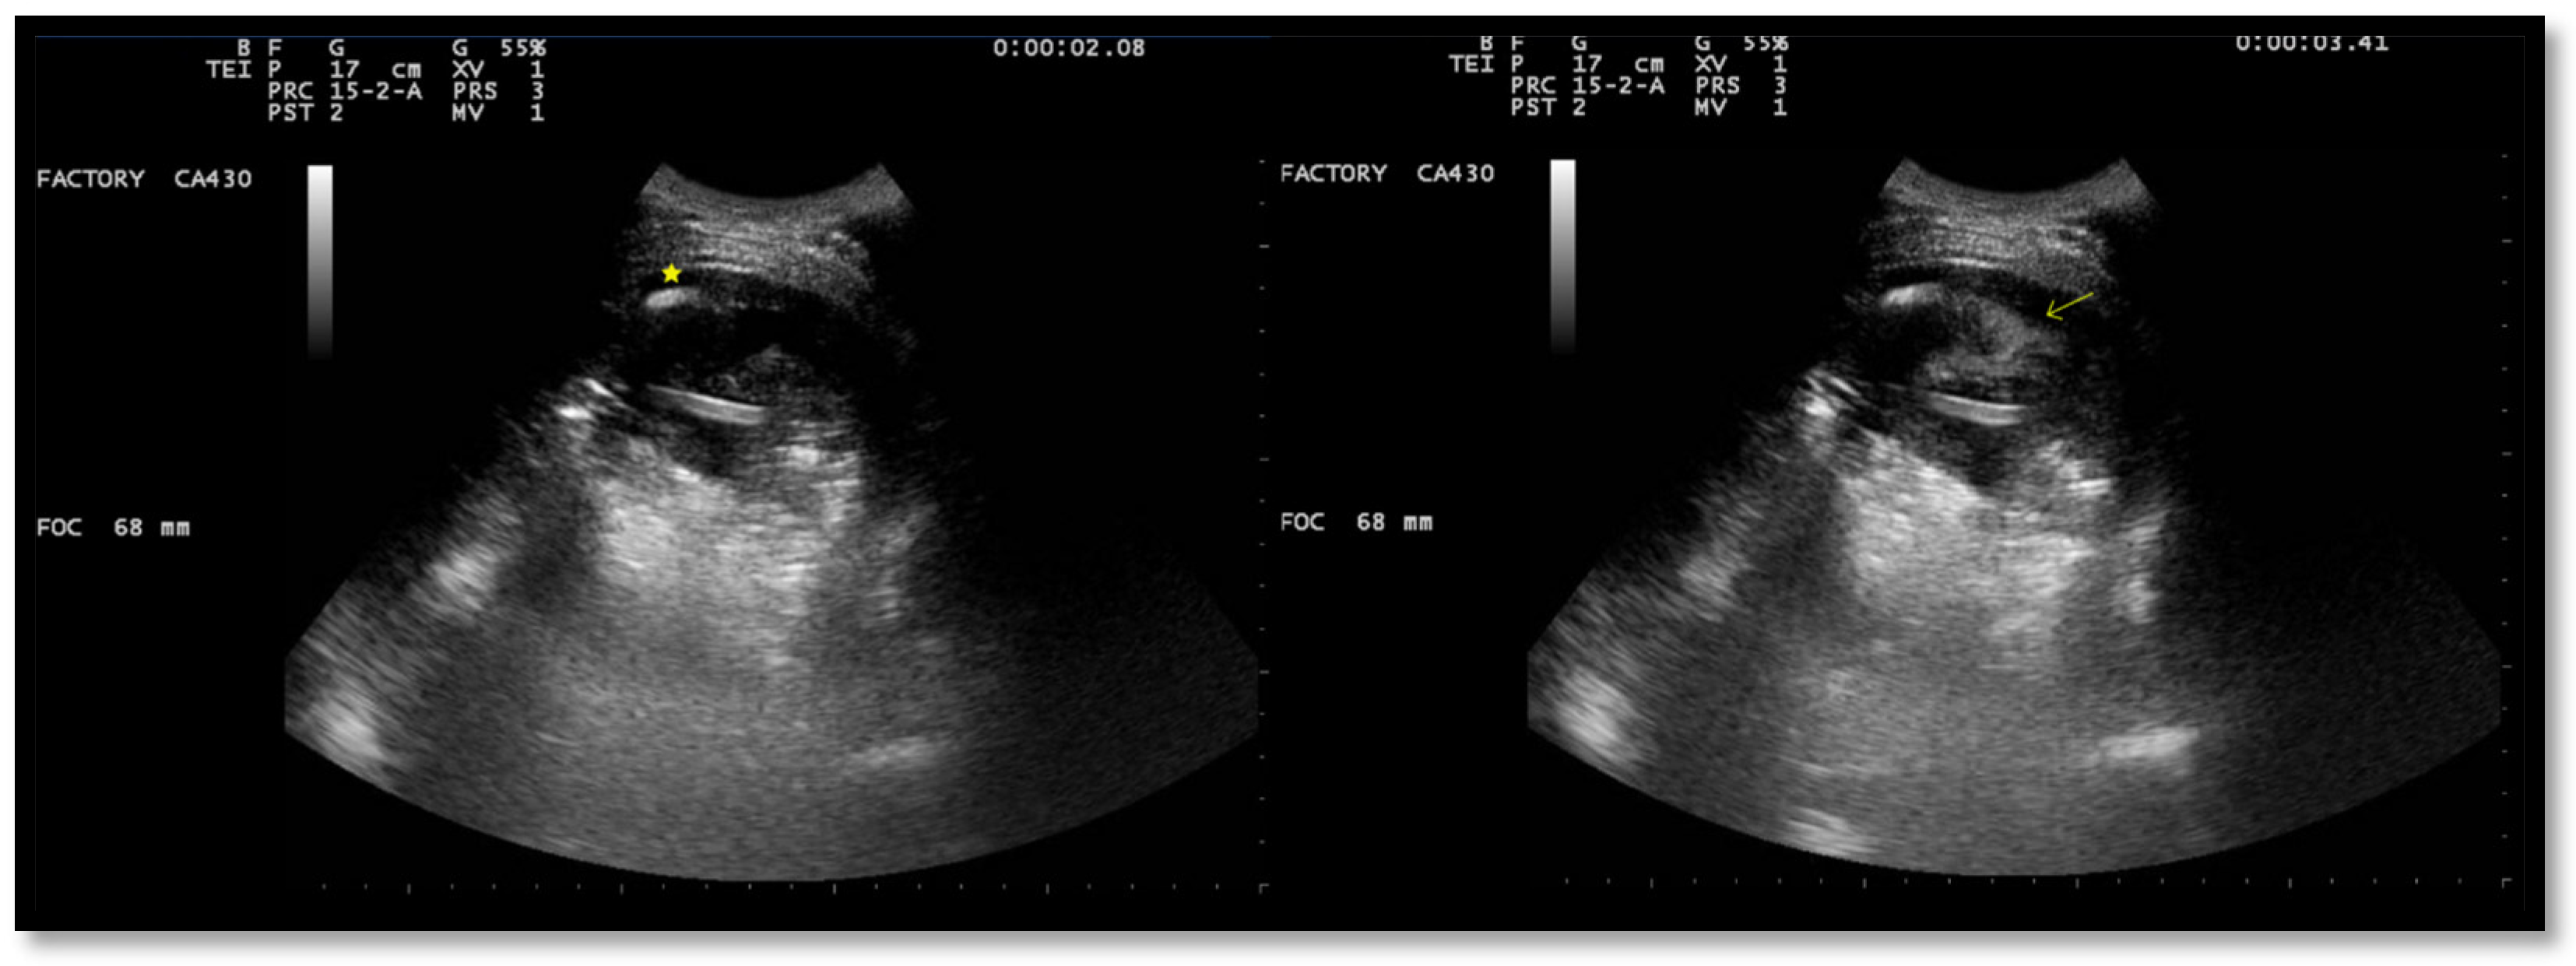

Figure 2. Chest US during pleural lavage with urokinase. Star: distal end of chest drain; Arrow: spread of fluid.

After the placement of a chest tube, pleural fluid samples were sent for microbiological and physicochemical analysis, which confirmed the diagnosis of pleural empyema. Two days after the placement of the chest tube, the fluid flow decreased. To break up the fibrin pockets present in the empyema and promote the complete evacuation of the fluid, irrigation of the pleural cavity with 200,000 UI of urokinase in 50 mL of saline solution was performed under US guidance (Figure 2).

Immediately following the instillation of the fibrinolytic agent, the chest drain was clamped for approximately 4 h. Then, irrigation with a few ml of saline solution was performed, and the chest tube was reopened. US observations 24 h after the intrapleural fibrinolysis showed a marked reduction in the extent of the effusion and localizations (Figure 3). After 72 h, the remaining fibrin sprouts had completely disappeared (Figure 3). This facilitated the drainage of the remaining exudate. At the same time, there was an improvement in his clinical condition with the disappearance of his fever and the restoration of normal oxygenation, which led to the discontinuation of oxygen therapy.